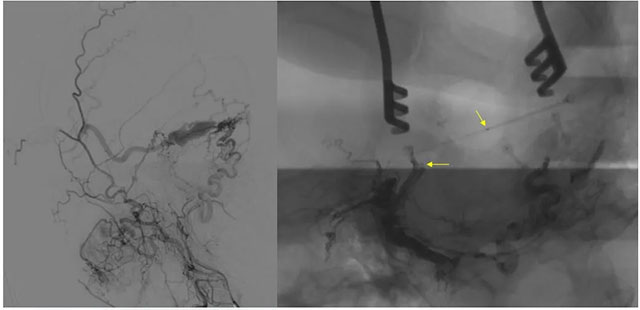

▲ 術(shù)前定位

8月23日,在復(fù)合手術(shù)室,在長(zhǎng)海醫(yī)院方亦斌教授指導(dǎo)下,張琪博士根據(jù)之前造影手術(shù)標(biāo)記點(diǎn)確定平行左側(cè)外耳道手術(shù)切口約 8cm,切開頭皮各層至顱骨,剝離骨膜,牽開,以咬骨鉗咬開一約 3cm 缺口,充分暴露橫竇。

▲ 造影確認(rèn)位置后,穿刺左側(cè)橫竇,置入 Echelon10 微導(dǎo)管

經(jīng)左側(cè)股動(dòng)脈以單彎造影管超選至左側(cè)頸總動(dòng)脈造影明確靜脈穿刺點(diǎn)入路,予以穿刺針穿刺成功后造影明確在位,隨后 Echelon 10微導(dǎo)管到位橫竇,填入一枚彈簧圈做塞子,造影明確位置后,緩慢注入 Onxy18膠 5毫升,鑄膠彌散良好,通過靜脈逆向彌散至部分供血?jiǎng)用}內(nèi)。復(fù)查造影,見瘺口完全被栓塞,引流靜脈消失,手術(shù)成功。